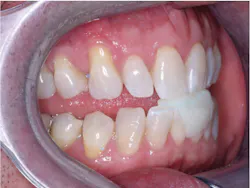

Dental sleep medicine is growing rapidly. Why? A large portion of the adult population in the US has an objectionable snoring problem. Do they want to quit snoring? Of course! Although most physicians place their snoring patients on a CPAP device, many patients are not compliant. Is there another way to stop snoring? Absolutely. You can do so with a well-made snoring appliance (figures 1 and 2).